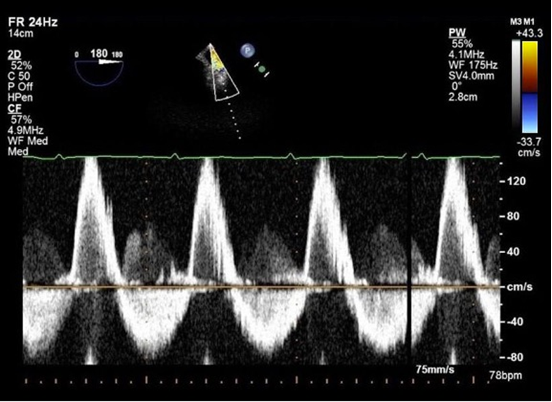

This Doppler trace obtained by transoesophageal echocardiography of the descending aorta (see far right) suggests:

a. Aortic dissection

b. Aortic stenosis

c. Aortic regurgitation

d. Normal flow

e. High flow state

A

AR - bidirectional

23.1 repeat